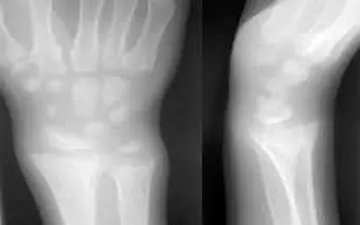

یک جراح و متخصص ارتوپدی گفت: استئومالاسی یا استخوان نرم به علت اختلال در معدنی شدن استخوانها در بزرگسالی ایجاد میشود…

نرمی استخوان به نرم شده و ضعیف شدن استخوان در کودکان گفته میشود که معمولاً بهدلیل کمبود شدید و طولانی ویتامین D…

راشیتیسم بیماری مربوط به رشد استخوانهاست که در نوزادان و کودکان مشاهده میشود و با مصرف برخی مواد غذایی میتوان آن…